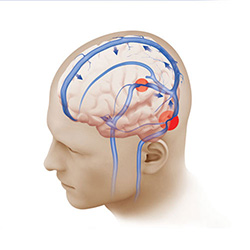

Investigated venous sinus stenting in patients with idiopathic intracranial hypertension, showing for the first time a quantitative reduction in intracranial pressure